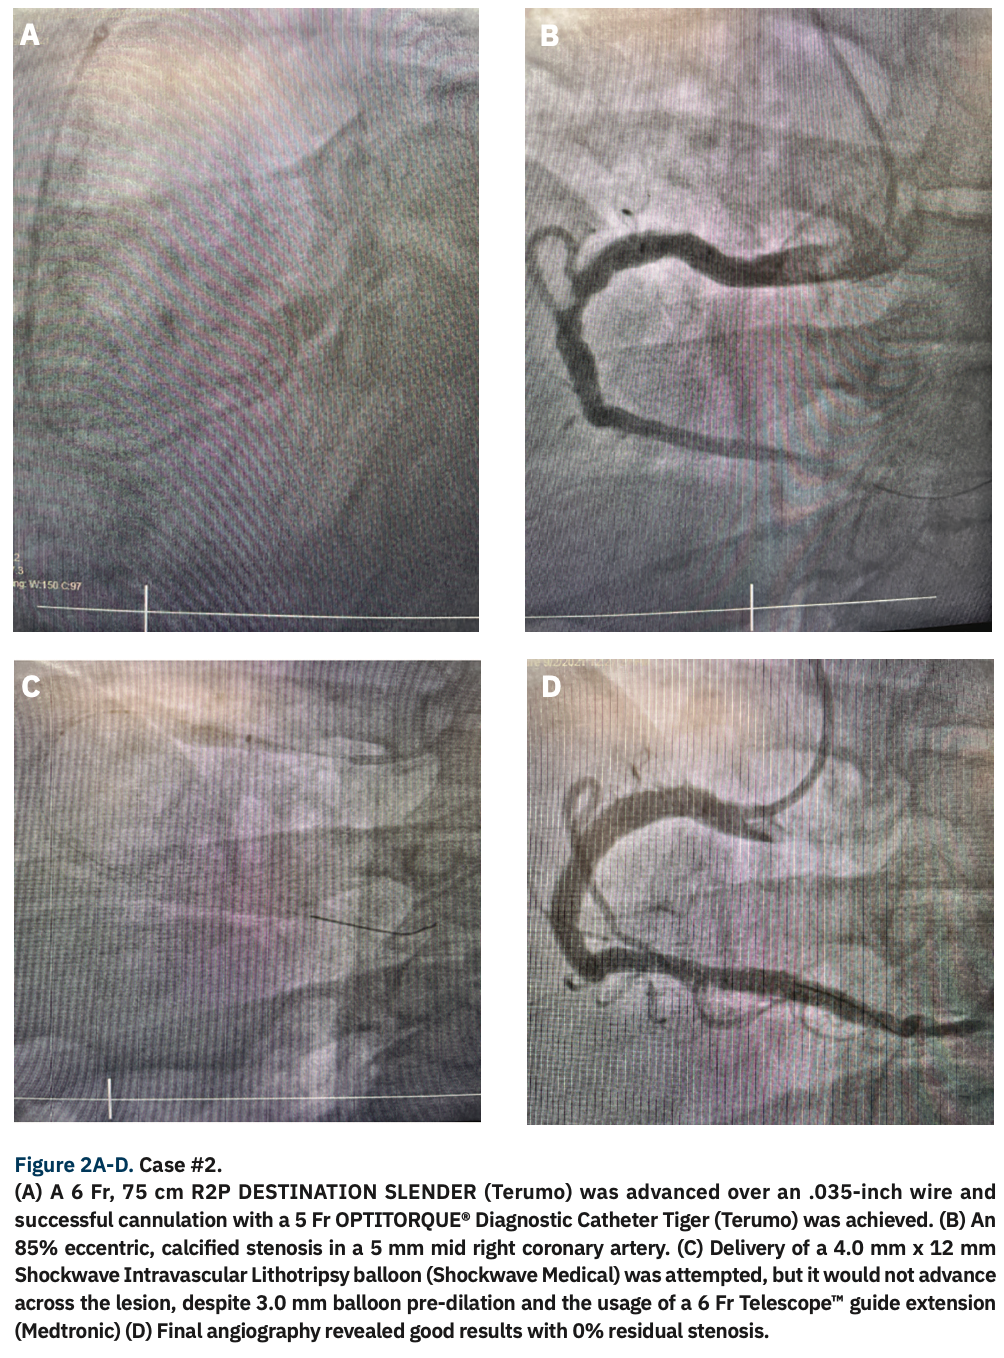

Vascular access was obtained at the right radial artery and a 5 Fr short GLIDESHEATH SLENDER was inserted using the original Seldinger technique. After injection of 2.5 mg verapamil and 200 mg nitroglycerin into the radial artery and full anticoagulation with heparin, the use of multiple coronary catheters was attempted, but we were unable to cannulate the coronaries due to severe tortuosity of the subclavian and innominate arteries. An alternative would normally have been switching to femoral access, but with limited hospital beds and short staffing due to COVID-19, we elected to avoid femoral access in order to limit the risks of complications and possible need of an overnight bed. Thus, a 6 Fr, 75 cm R2P DESTINATION SLENDER was advanced over an .035-inch wire and successful cannulation with a 5 Fr OPTITORQUE® Diagnostic Catheter Tiger was performed (Figure 2A). Angiography demonstrated an 85% eccentric, calcified stenosis in a 5 mm mid right coronary artery (RCA) (Figure 2B). The RCA came off low on the right coronary cusp, so an Amplatz left (AL)1 guide was chosen for extra backup, and we were able to cannulate the vessel successfully. A Runthrough® NS wire (Terumo) was advanced to cross the lesion. Delivery of a 4.0 mm x 12 mm Shockwave Intravascular Lithotripsy balloon (Shockwave Medical) was attempted, but would not advance across the lesion, despite 3.0 mm balloon pre-dilation and the usage of a 6 Fr Telescope™ guide extension (Medtronic) (Figure 2C). We decided to proceed with orbital atherectomy, performed with a 1.25 mm Diamondback 360® crown (CSI). The Shockwave balloon was too kinked to be readvanced, so we advanced a 5.5 mm x 26 mm Onyx™ stent (Medtronic) that crossed the lesion and was deployed successfully. Post dilation was performed with a 5.5 mm noncompliant Emerge™ balloon (Boston Scientific). Final angiography revealed good results with 0% residual stenosis (Figure 2D). The patient was discharged home after 4 hours. A safe and efficient radial technique with the use of a long R2P Destination Slender allowed us to perform a complex radial intervention, despite difficult upper extremity anatomy and tortuosity.